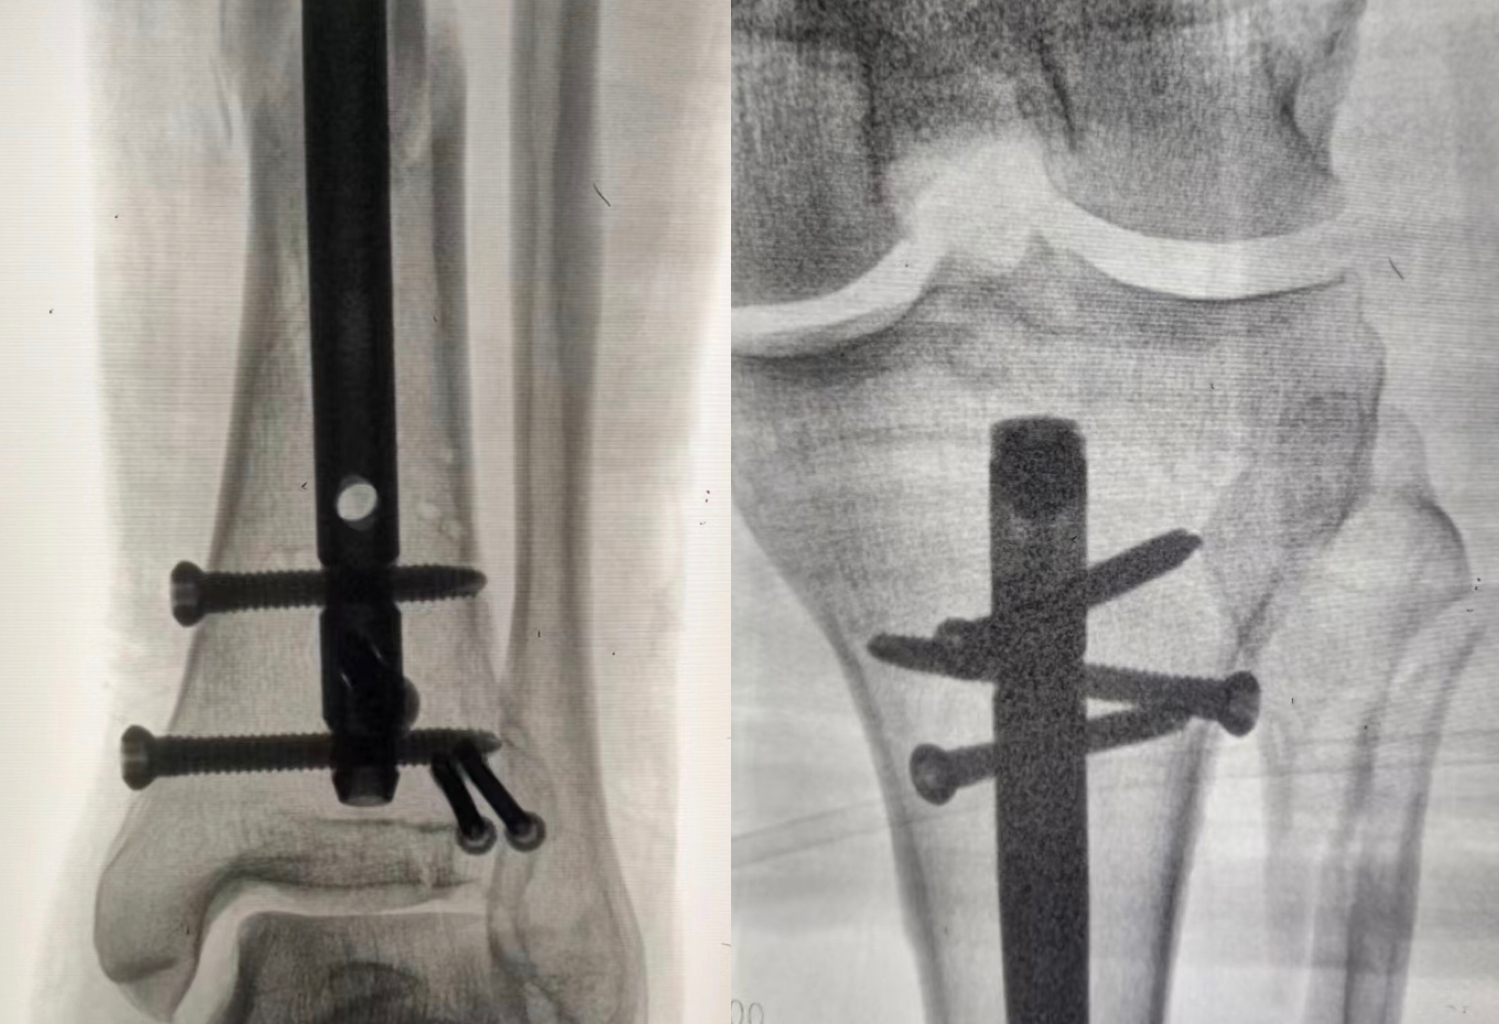

病例一:患者,女,70岁,车祸致左肱骨近端粉碎骨折,在孙院长组织术前讨论后决定行”左肱骨近端粉碎性骨折闭合复位髓内钉内固定术”考虑患者年龄大、基础病较多,微创治疗恢复快,骨三科医疗团队为其行手术治疗,术后功能恢复良好,患者及家属十分满意。 ▲术前 ▲术后 病例二:患者,男,51岁,因滑倒摔伤致左胫腓骨骨折伴后踝骨折,术前准备钢板内固定、髓内钉闭合内固定两种手术方案,通过术前讨论和局部皮肤条件的观察,选用髓内钉闭合复位内固定,骨三科医疗团队主刀下运用多枚克氏针(阻挡+固定+合拢),解决后踝和螺旋劈裂骨折块问题,手术顺利结束。 ▲术前 ▲术后 ▲术后 ▲术后微创小切口 目前,我院骨三科医疗团队已成功完成数例髓内钉手术,临床疗效非常满意。近年来周口人合医院骨三科大力发展微创技术,积极开展各类微创手术,力求打造微创以及快速康复的治疗新标杆,更好地为人民健康保驾护航。 ▲创伤与手足显微外科专家查房查看患者病情 ▲创伤与手足显微外科专家共同探讨患者病情